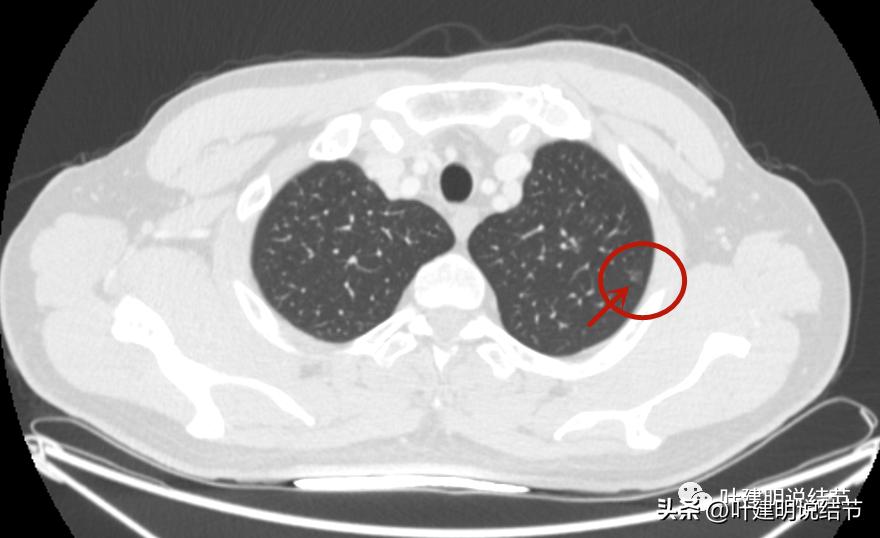

病灶1:左上叶结节

中间密度比周围区域更低一点。

瘤肺边界清。

感觉之所以中间密度偏低,是不是因为病灶边上有血管,从而血管围成类近一圈,而肿瘤的真实部分密度是非常低的,看上去显得低密度空泡征似的?

周围不同方向也有血管。

左侧磨玻璃结节红色圈起来的瘤肺边界清,有血管贴边,但整体密度低,没有实性成分,考虑仍是不典型增生或原位癌阶段,近期风险低,个人觉得最好先随访,因为可能很多年不变的,而且也可能再检出新的结节来。况且随访有进展再干预,效果也是一样的。右侧结节也是肿瘤范畴,但风险一样不高,建议同样半年到一年复查(其实1年也关系不大的)。意见供参考!